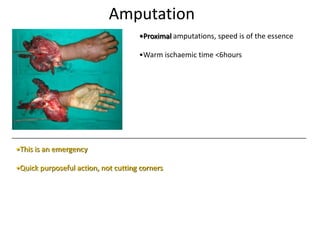

- Conditions that require emergency referral are discussed, such as bleeding, amputation, replantation, compartment syndrome, infections, and high pressure injection injuries. Proper management of these conditions focuses on rapid assessment and treatment to prevent further tissue damage.